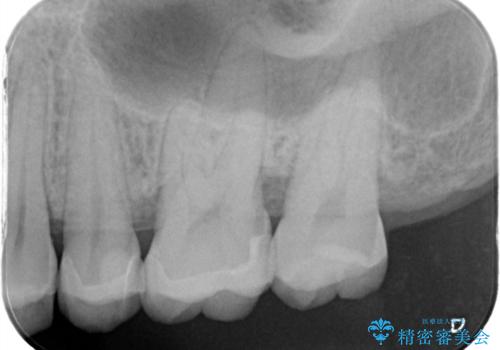

- 歯が欠けたということで来院された患者様です。

診断した結果、昔つめたプラスチックの材料が劣化し割れてしまったことが原因でした。

そのためセラミックれの治療を進めました。

前詰めていたやつをきれいに取り、セラミックにすることによって適合のいいものになりました。色も満足していただけました。